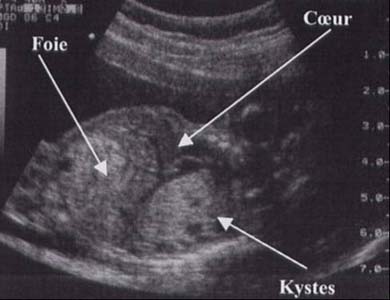

MAKP - macrokystique